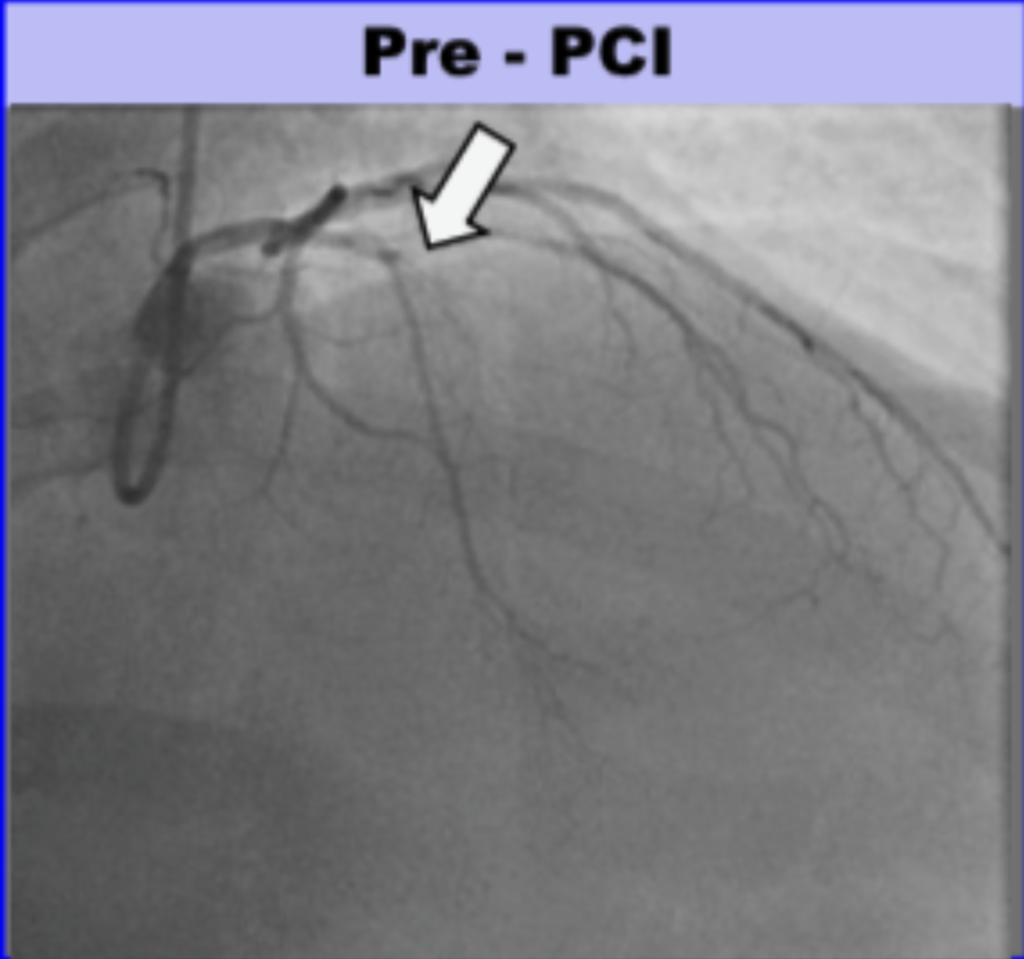

Angiogram

- There was a 100% ostial (very proximal) LAD occlusion. According to the schematic below, the occlusion was proximal to the septal perforator, with Septal OMI just as predicted. Frankly, it does not look like that to me but I am far from expert at angiograms.

Here is the angio before and after PCI, and a schematic: